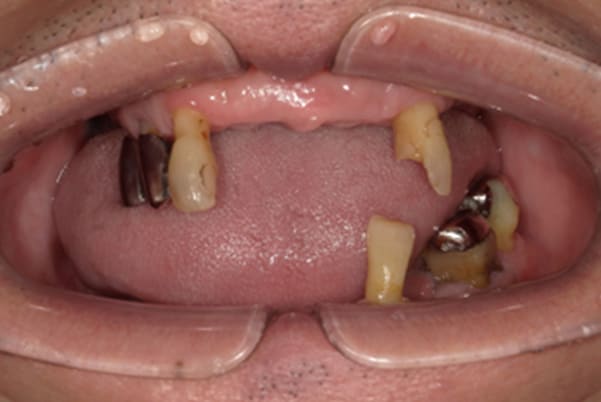

症例レポート[CASE.04]

前歯がとれて痛い、

食事もできず、見た目も悪い

- 女性(60代)

- 前歯がとれて、痛い、食事ができない、見た目が悪く人に会えないので何とかしてほしい

- 上顎精密金属総入れ歯

- 下顎精密金属部分入れ歯

- 磁性アタッチメント(白金加金) 1歯

上前歯はブリッジの差し歯により根が折れ炎症を起こしお痛みのある状態でした。

原因は長期使用により下の義歯の歯が削れたことにより、下前歯が上前歯を突き上げ強い力が加わっていたことが根本的な原因と考えられます。

治療前は、奥歯が下がり、かみ合わせが乱れています。適切な入れ歯はそのままのかみ合わせで義歯を作るのではなく治療後のように、前歯から奥歯までのラインが真っすぐ揃った、かみ合わせの面を適切に付与し、よく咬め、残りの歯に負担がかからないかみ合わせとしました。

とにかく何も食べられないこと、人に会えないことから、なるべく早く何とかしたいとのご希望でした。

患者様とご相談の上、まず早急に上記を回復させるため、初診含め3度の来院でお食事ができ、見た目を回復できるように治療用義歯を作製、装着しました。

本来は、数本の上前歯の折れてしまって残せない歯は抜いてから歯肉の治癒を待ち、数か月後に型どりから作製になりますが、抜歯即時義歯といって、歯を抜く前に型、かみ合わせをとり、抜歯を行ったその日に上下の義歯を装着する特殊な治療法を用いたことで、10日後には治療用義歯をお口に装着することができ、お痛みもなくお食事ができ、ご友人とのお食事にも行けることが可能になりました。

本来、入れ歯作製は技工所と言って、義歯を作製する所に発送するため、作製には時間がかかりますが、院内に技工専用スペースを完備しており、長年、義歯治療において、技工も技術の習得してきましたので技工士さんではなく、かみ合わせの道具も私自身で院内で作製したことで、初診日の次の日にご来院いただきかみ合わせを採ることで、診断、型どり、かみ合わせ、装着まで10日という最短のご希望にこたえらた方です。

上顎治療前

-

上顎治療後

根のみの7本は虫歯にもなっており歯肉は腫れあがっています。

残りの歯もレントゲンで重度の歯周炎によりぐらぐらな状態でした。